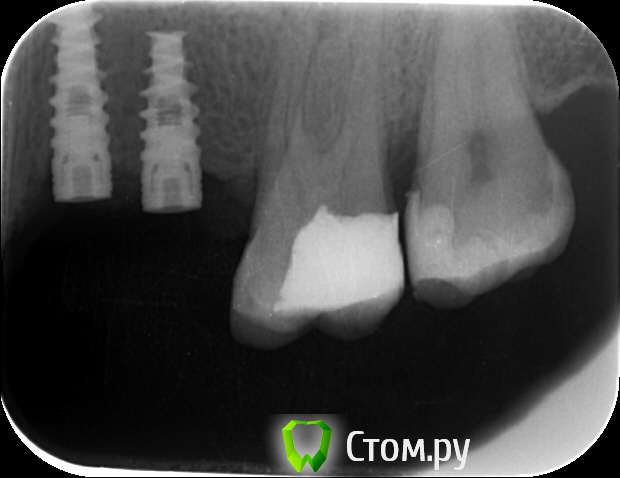

an_ver Опубликовано 12 сентября, 2014 Автор Поделиться Опубликовано 12 сентября, 2014 Вот снимки Ссылка на комментарий

an_ver Опубликовано 12 сентября, 2014 Автор Поделиться Опубликовано 12 сентября, 2014 На момент установки Ссылка на комментарий

k.t.m. Опубликовано 12 сентября, 2014 Поделиться Опубликовано 12 сентября, 2014 длина имплантата 6мм или ракурс такой? Ссылка на комментарий

an_ver Опубликовано 12 сентября, 2014 Автор Поделиться Опубликовано 12 сентября, 2014 (изменено) длина имплантата 6мм или ракурс такой?Не, 8 мм.У Альфы на станд.платформе нет 6 мм,только на широкой Изменено 12 сентября, 2014 пользователем an_ver Ссылка на комментарий